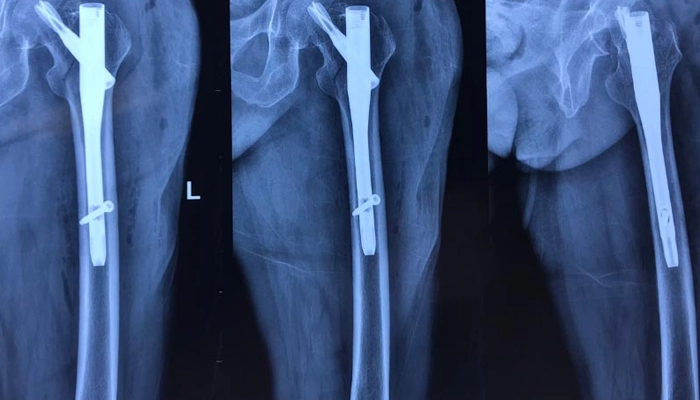

Phẫu thuật đóng đinh nội tủy: Sử dụng các loại đinh đặc biệt (đinh có thể kéo dài theo sự phát triển của xương - telescoping rods) đặt bên trong lòng xương để định hình, ngăn ngừa biến dạng và hỗ trợ chịu lực.

Bác sĩ có thể chỉ định phẫu thuật đóng đinh nội tủy khi cần thiết